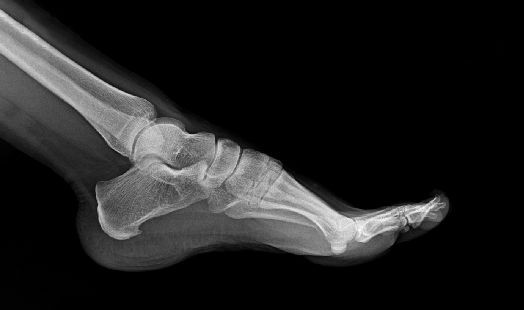

Qu'est-ce qu'une épine calcanéenne ?

Une épine calcanéenne est une excroissance osseuse qui se forme au niveau de l'os du talon. Cette excroissance fine et longue (d’où le nom d’épine) apparaît sous cet os, dans la zone où s'insère la membrane fibreuse qui relie le talon à la base des orteils. Cette membrane soutient l'ensemble du pied et transmet la force nécessaire à la propulsion du pied de l'arrière vers l'avant lors de la marche. Lorsqu’elle est trop sollicitée, il se crée une inflammation à l’endroit où s’insère cette membrane et cette inflammation peut conduire à la formation de cellules osseuses. En s’accumulant, cette calcification de la membrane forme une épine, dénommée épine calcanéenne, épine de Lenoir ou exostose calcanéenne.

Comment diagnostiquer une épine calcanéenne ?

Une radiographie permet de diagnostiquer cette pathologie et de pouvoir mettre en place une bonne prise en charge qui passera par un rendez-vous chez le médecin, le kinésithérapeute et si besoin le podologue.